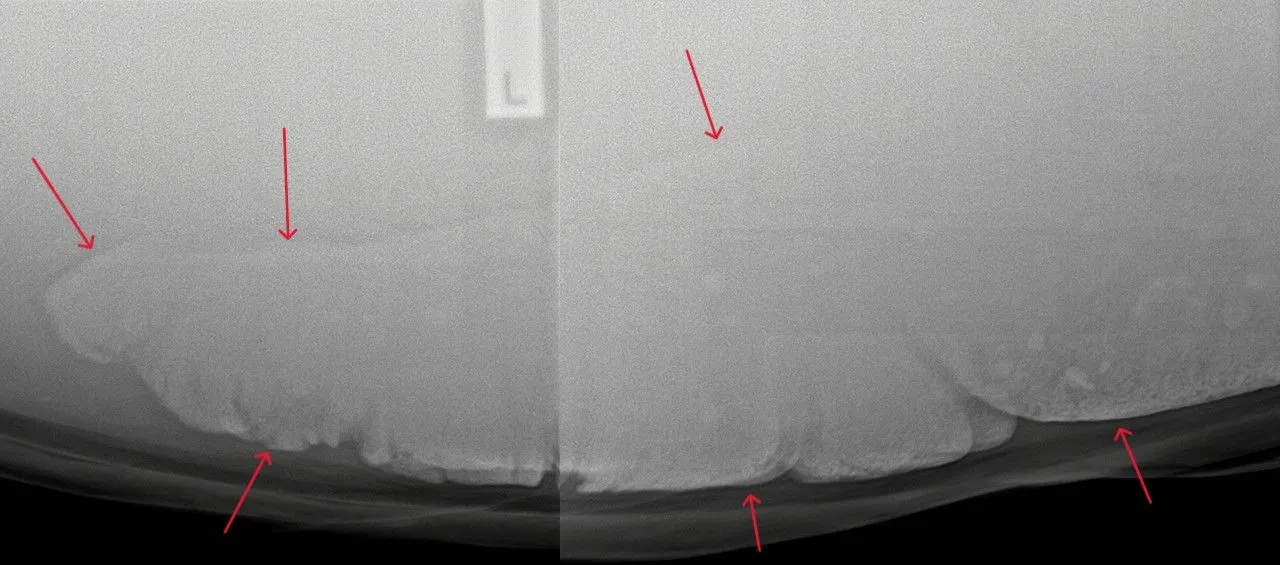

You may commonly see your veterinarian auscultate your horse for sand (listen to its abdomen with a stethoscope). When sand is moving within the digestive system, it sounds like ‘waves on the beach’, which is what we are listening for! It is important to note, however, that auscultation can only confirm if sand is present and cannot be used to completely rule out the presence of sand. We have seen many cases where no sand is auscultated; however, we know the horses are full of sand, and it has been confirmed on radiographs.

The best way to diagnose sand is abdominal radiographs, which can confirm the presence of sand and also the quantity of sand. These can be performed at your dental appointment, please just let us know at your appointment.

This information can then be used to formulate an appropriate treatment plan. Before-and-after radiographs can also help determine the success of a treatment plan and ensure the sand has actually been removed.